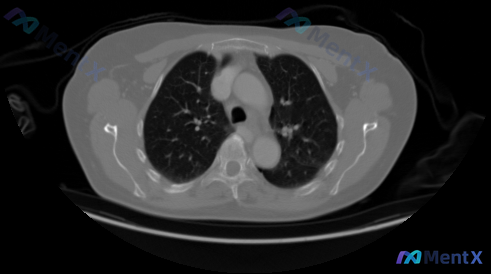

整理了一份很有意思的“阴性病例”分析思路——不是分析发现了什么,而是分析“没发现什么”时该怎么思考。 先看影像资料 这是一张胸部CT肺窗横断面图像(双肺上野层面): - 肺实质与气道:肺纹理清晰走行自然,未见实性结节、磨玻璃结节或肿块影,未见异常浸润影、间质改变;各级支气管管腔通畅,管壁无增厚,无支...